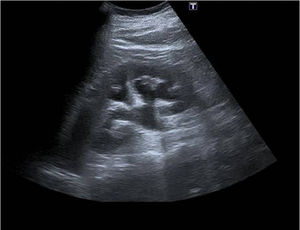

Varón de 50 años, asintomático, con antecedentes de diabetes mellitus, hipertensión arterial, dislipemia y tabaquismo, en tratamiento con enalapril/hidroclorotiazida 20/12,5mg, rosuvastatina 20mg y metformina 850mg. Acude a consulta para realizar analítica de control, en la que se observa microhematuria (21-30 eritrocitos/μl). Se repite la analítica, apareciendo nuevamente en el sedimento hematíes con cristales de oxalato cálcico y urocultivo negativo. Se realiza ecografía abdominal, donde se observa dilatación de los 3 sistemas colectores y la pelvis renal izquierda, hallazgos compatibles con hidronefrosis renal izquierda leve. No se visualizan cálculos ni masas renales y la vascularización renal es normal en el estudio doppler color (fig. 1). Se deriva a urología, donde se realiza tomografía axial computarizada (TAC) que muestra una moderada dilatación pielocalicial del riñón izquierdo con infundíbulos de 12mm y pelvis renal de 32mm. El riñón presenta un tamaño normal, con parénquima renal conservado, observándose retraso en la eliminación del contraste intravenoso. El uréter proximal también está dilatado, con un calibre de 9mm, identificándose un cambio brusco de calibre a la altura del cruce con los vasos ilíacos, sin encontrarse litiasis ni engrosamiento focal significativo de su pared. Se visualiza un aumento de partes blandas bien definido rodeando a la aorta abdominal infrarrenal y las arterias ilíacas comunes, con mínima afectación de la grasa circundante. En la región de la ilíaca común izquierda dicho aumento de partes blandas contacta con el uréter izquierdo. En su conjunto estos hallazgos son compatibles con una fibrosis retroperitoneal (FR), con infiltración del uréter izquierdo y uropatía obstructiva secundaria (fig. 2). Se realiza cateterismo ureteral mediante derivación urinaria con doble J y se pauta tratamiento con corticoides orales, que ocasionan varias descompensaciones hiperglucémicas. Ante la presencia de lumbalgia asociada y como tratamiento definitivo, se realiza ureterólisis y omentoplastia del uréter izquierdo a nivel del cruce ilíaco. Tras retirar el catéter doble J, el paciente realiza revisiones periódicas y se mantiene asintomático.

El diagnóstico es difícil y tardío por su instauración insidiosa. Además, las pruebas de laboratorio (elevación de PCR, VSG, creatinina y urea) son inespecíficas. Por eso, las pruebas de imagen son imprescindibles para su detección. La ecografía es útil como primera prueba de imagen por su fácil acceso y rapidez para detectar hidronefrosis, aunque es poco sensible para identificar la placa fibrótica. Se puede observar una estructura hipoecogénica fusiforme alrededor de los vasos retroperitoneales5. En la actualidad, gracias a técnicas de ultrasonidos como los armónicos que reducen los artefactos y aumentan la resolución de la imagen, la detección de la placa fibrótica es más precisa, especialmente a nivel de la bifurcación aórtica6. La TAC con contraste es la técnica de elección para el estudio de la vía urinaria superior, y conocer la morfología y la extensión de la placa fibrótica. La resonancia magnética permite distinguir causas benignas y malignas de la FR. La placa fibrótica aparece como una lesión hipointensa en T1 y de intensidad variable en T2. En la FR de causa benigna la placa es de menor tamaño y tiene contornos lisos, el uréter presenta desviación medial y la aorta y la vena cava inferior no están desplazadas. Cuando la FR es secundaria a un proceso maligno, la masa fibrótica tiene bordes irregulares, desvía lateralmente el uréter y produce elevación de la aorta y la vena cava inferior respecto a la columna vertebral. La confirmación histológica mediante biopsia es necesaria en la FR de localización atípica, ante la sospecha de una causa maligna o en caso de ausencia de respuesta al tratamiento1,5.